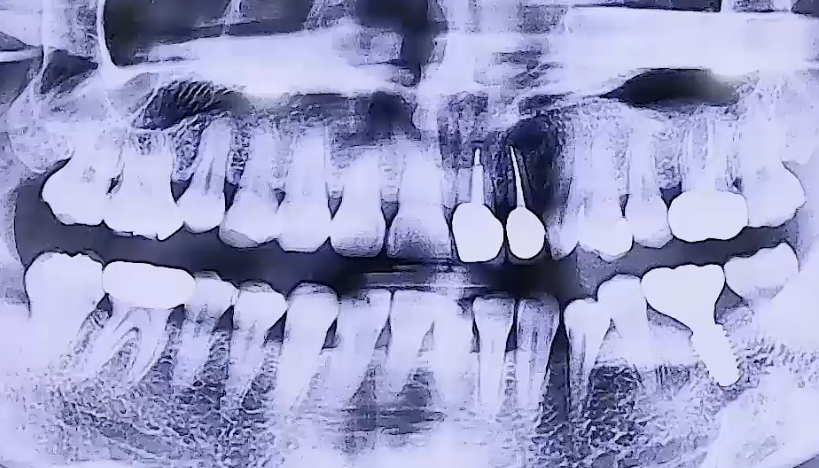

AFTER

왼쪽 아래 어금니 통증으로 내원해주신 환자분이십니다.

왼쪽 아래 뒤에서 두번째 큰 어금니를 타 치과에서 신경치료 후

보철치료까지 마무리하신 상태였는데, 그 주변 잇몸에 염증이 생기며

굉장히 부어 오르고 통증이 심했던 것으로 확인되었습니다.

해당 치아는 겉으로는 보이지 않는 잇몸 속에 염증이 생긴 것이기 때문에

잇몸치료를 해도 치아가 안 좋아질 가능성이 크므로 발치 후 임플란트를 결정하였습니다.

또한 위 앞니는 깨져있어서 기둥을 세우고 치아를 복원하는 보철치료를 진행하였어요.

오른쪽 아래 매복사랑니가 앞쪽 치아를 향해 옆으로 누워 아주 조금 나와 있어,

그쪽에 음식물이 끼면서 염증이 생길 수 있기 때문에 발치를 해드렸습니다.